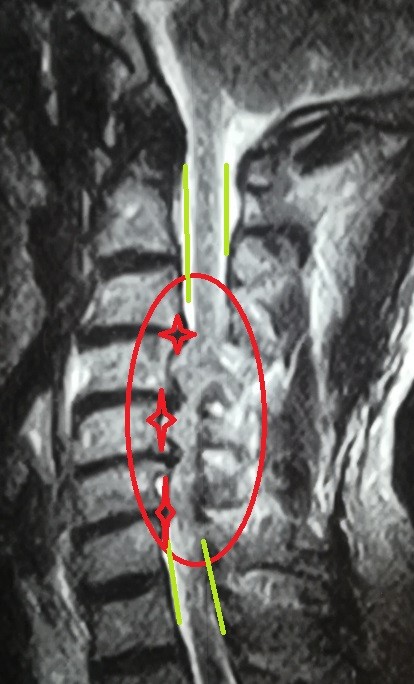

A successful surgery was performed to decompress a narrowed cervical spinal canal. This condition occurs when the spinal canal in the neck area narrows, causing pressure on the spinal cord and nerves supplying the arms and hands.

• Expanding the narrowed spinal canal in cervical vertebrae

• Relieving pressure on spinal cord and nerves

• Accurate preoperative planning using advanced imaging